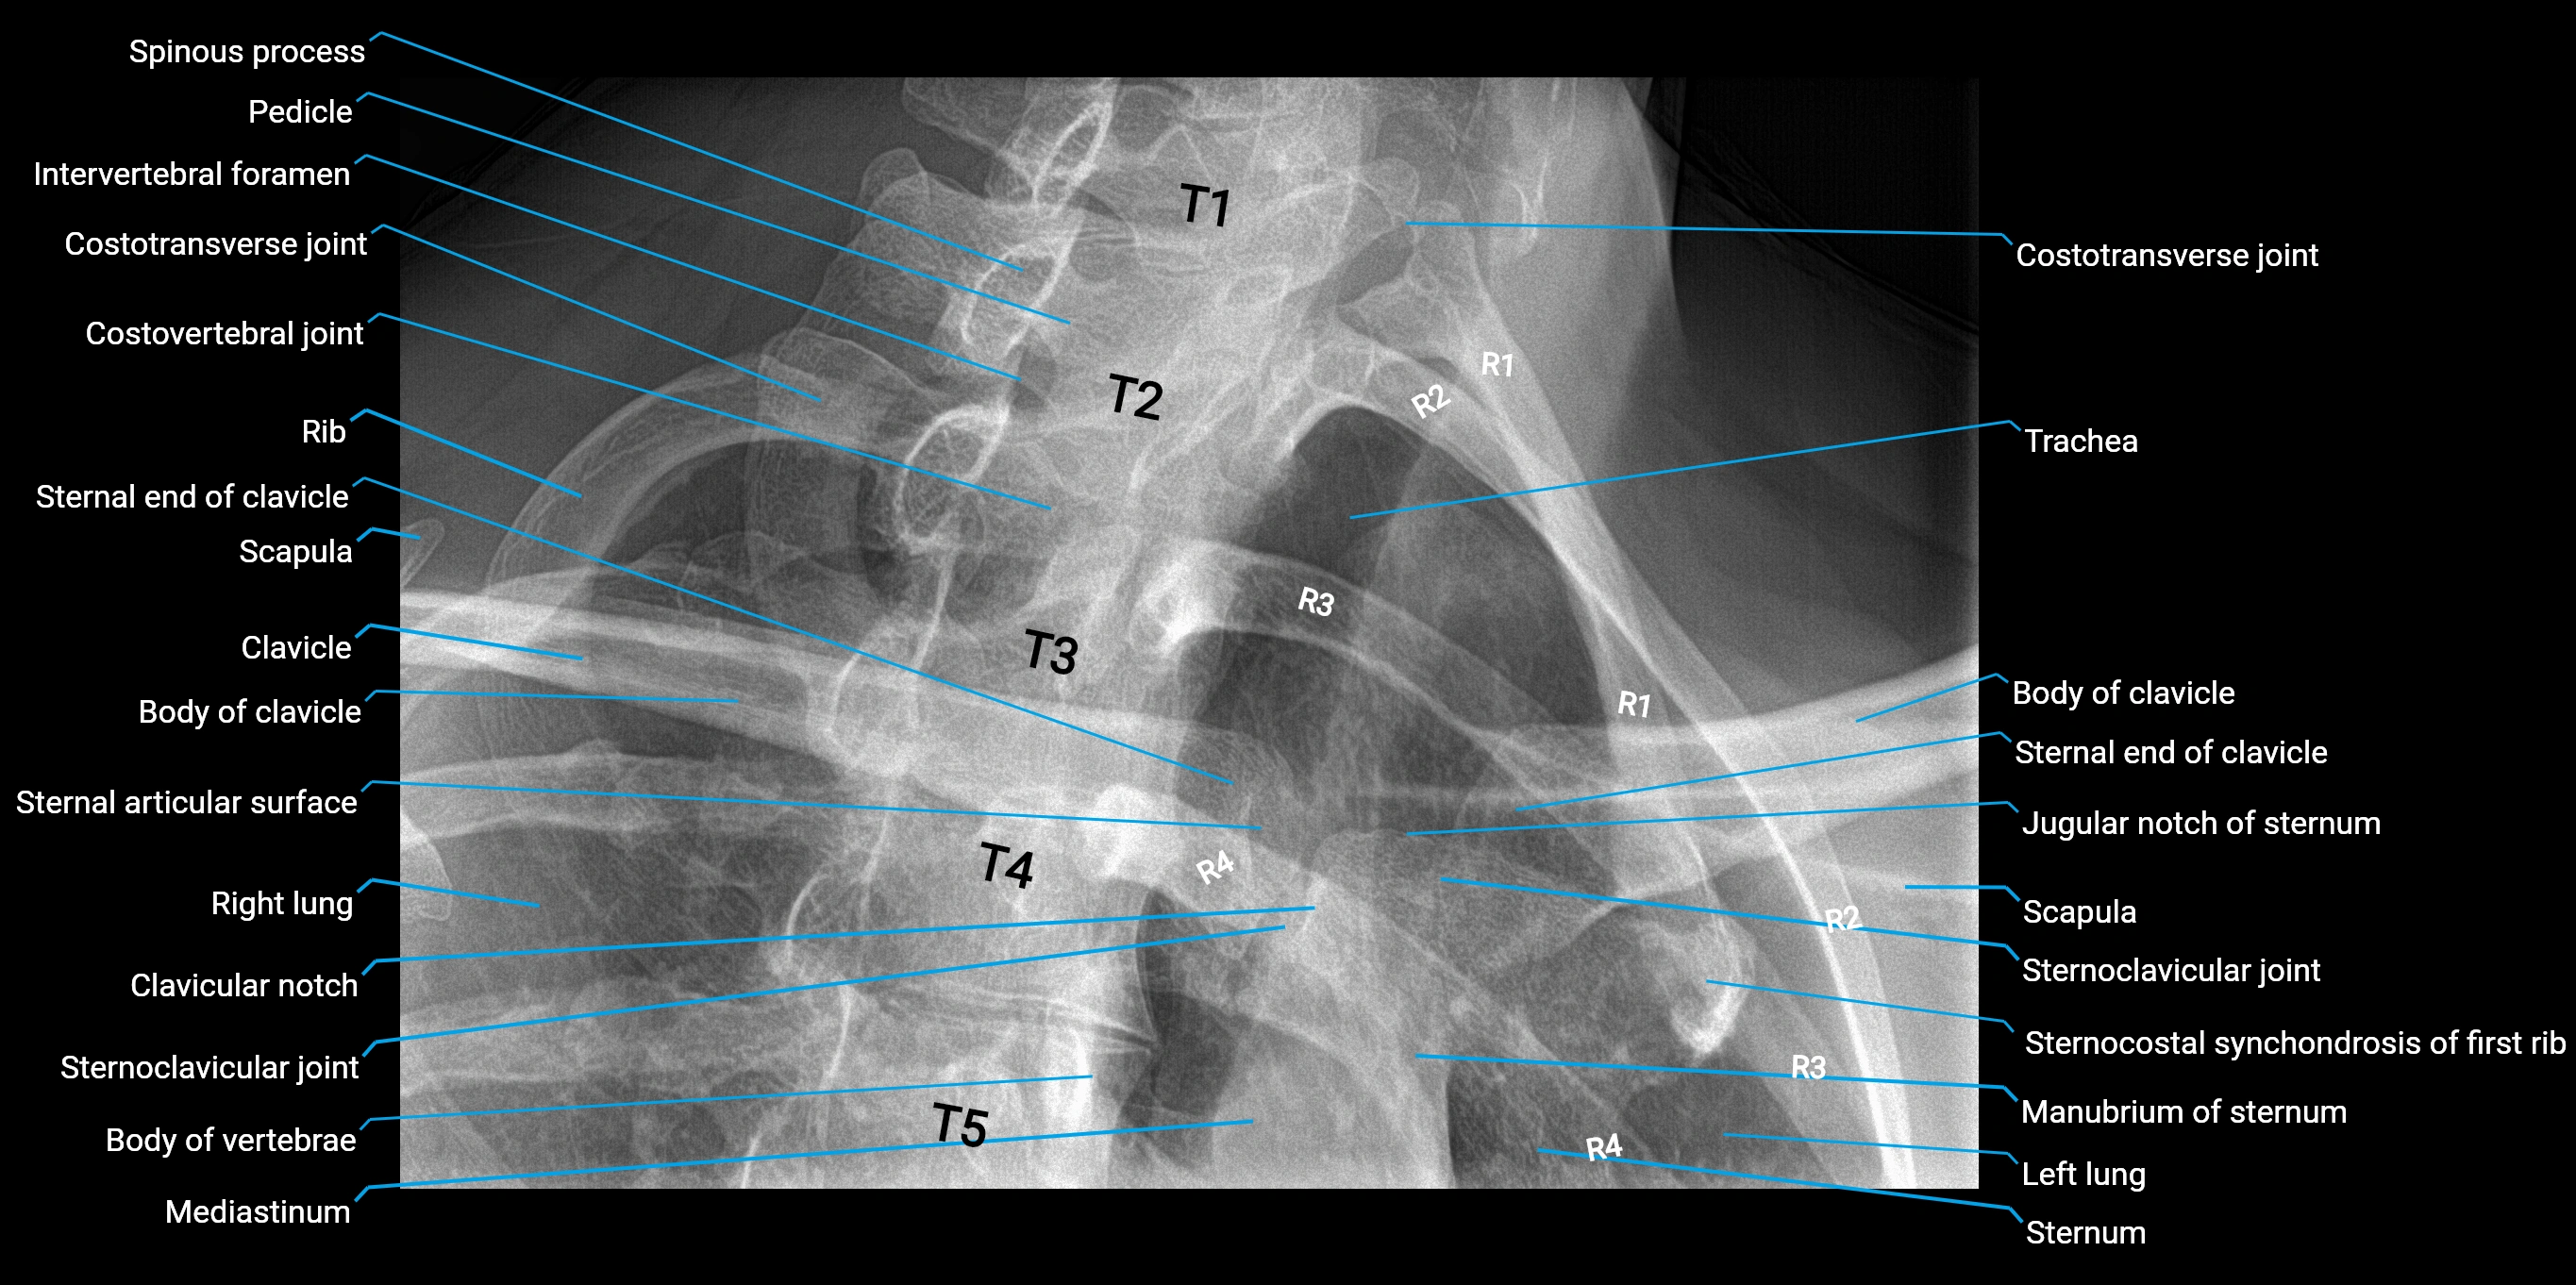

X-Ray image

image